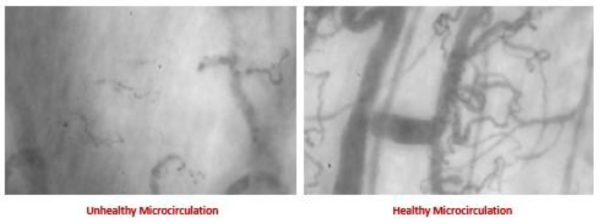

At Truhealth, we emphasize vascular health as a cornerstone of longevity. One of the most important yet overlooked structures in the body is the Endothelial Glycocalyx a microscopic, gel-like lining inside your blood vessels that keeps them flexible, protected, and free of inflammation. It’s the largest organ in your body 60,000 miles / 7,800 sq ft of microvascular capillaries.

It regulates circulation, oxygen delivery, nutrients exchange, and inflammation.

Damage to the Glycocalyx can impair blood flow and accelerate aging

GlycoCheck™ Testing

We offer GlycoCheck™, a simple, non-invasive test that evaluates your glycocalyx health in real time. The handheld device, gently placed under the tongue, analyzes tiny blood vessels to assess microvascular health, inflammation, and early signs of vascular aging.

Results help us create a personalized plan to restore and protect your vascular system.

Longevity Starts with Healthy Circulation

Your vascular system impacts every organ—brain, heart, kidneys, gut, and skin. Protecting the glycocalyx supports not only cardiovascular health but your overall vitality and longevity.

ReVascais a comprehensive circulatory supplement that works in two powerful ways:

1. Restores Microcirculation:

ReVascaTM repairs the tiny capillaries and vessels in your microcirculatory system. These capillaries are responsible for oxygen and nutrient delivery to every cell and the removal of toxins. By revitalizing these small blood vessels, ReVascaTM improves overall cellular health and function.